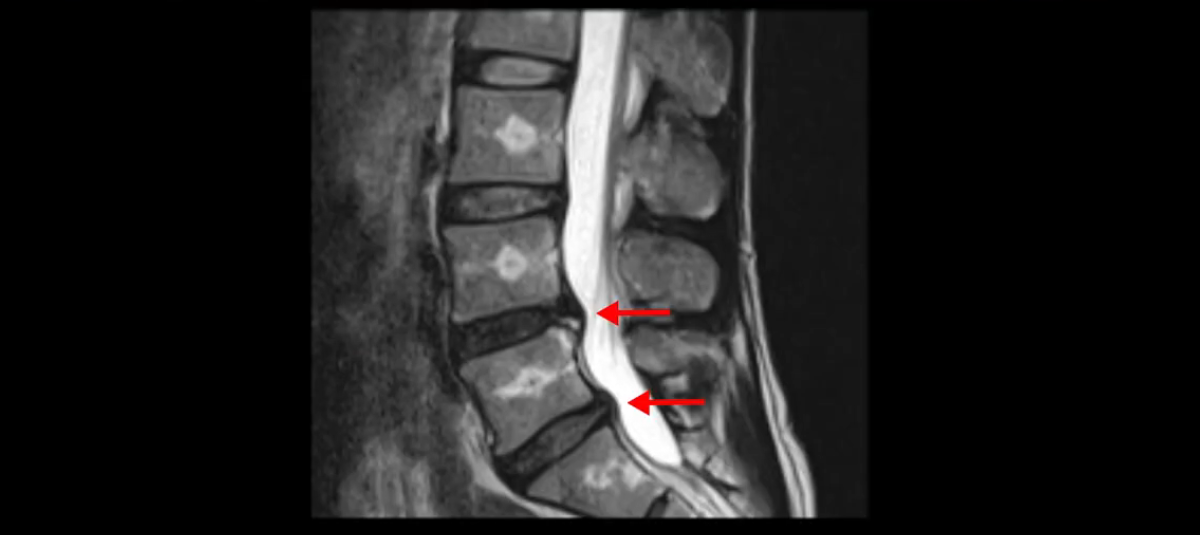

우선 이분의 MRI를 보고 먼저 설명을 드린 후 이런 환자분들의 통증의 원인은 무엇인지, 그리고 치료는 어떻게 해야 하는지 자세히 설명 드리겠습니다.

이분 MRI를 보시면 두 마디의 퇴행성디스크가 있습니다. 그리고 디스크가 조금씩 밀려 나와 있고요. 그런데 디스크 탈출 정도는 두 마디 다 심하지 않습니다. 4번 5번에는 디스크 탈출이 약간 있고,

척추관협착도 약간 진행이 되고 있고요.

5번 1번은 디스크 탈출이 가운데 쪽으로 살짝 있습니다.

또한 양쪽 신경 가지가 빠져나가는 추간공은 매우 넓은 상태입니다.

중요한 것은 이 정도 경미한 탈출과 협착으로는 양쪽 다리가 저리고 아플 수가 없습니다.

그리고 만약에 이 디스크가 급성으로 찢어진 것이라면 아주 심한 디스크성 통증이 있겠죠. 기침이나 재채기를 하면 심하게 아프고 허리를 조금만 구부려도 아주 날카로운 통증들이 생길 겁니다. 그런데 이분은 이런 증상이 전혀 아닙니다. 디스크의 돌출 정도와 협착이 전혀 심하지 않기 때문에 이분이 가지고 계신 양쪽 다리 저림, 특히 이분은 누워있을 때도 양쪽 다리가 저리다고 하는데, 디스크 때문에 그런 증상은 생길 수가 없습니다. 또 이 디스크는 오래된 디스크, 이미 찢어진 섬유륜이 아문 디스크이고, 그러니까 이분은 기침이나 재채기를 못하는 증상이 없는 거죠. 그 다음에 허리를 구부릴 때 뻐근한 증상은 있지만 아주 날카로운 통증은 없습니다.

이분 MRI를 보시면 퇴행성디스크가 있고 약간의 협착이 있지만 이 정도의 퇴행성디스크와 협착으로는 신경이 눌려서 양쪽 다리가 저리고 아픈 증상이 나올 수가 없습니다. 그래서 MRI와 이 환자분의 다리 증상이 매치가 안 된다고 하는 의사들이 많은 겁니다.